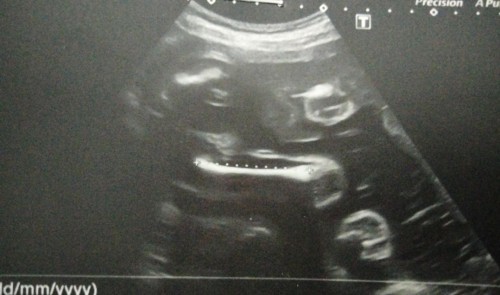

ภาพนี้ตอน28weeksค่ะ ตอนนี้32+3แร้วจ้า #ลูกสาวจ้า

ซาวด์ตอน30วีค ตอนนี้33w 4dแล้วค่ะ #ลูกสาว

ซาวด์เมื่อ2วันที่แล้ว วันนี้12วีคพอดีเลยค่ะ🥰

ภาพซาวด์ดูเพศล่าสุดตอน20วีคค่ะ ตอนนี้23วีคแล้ว